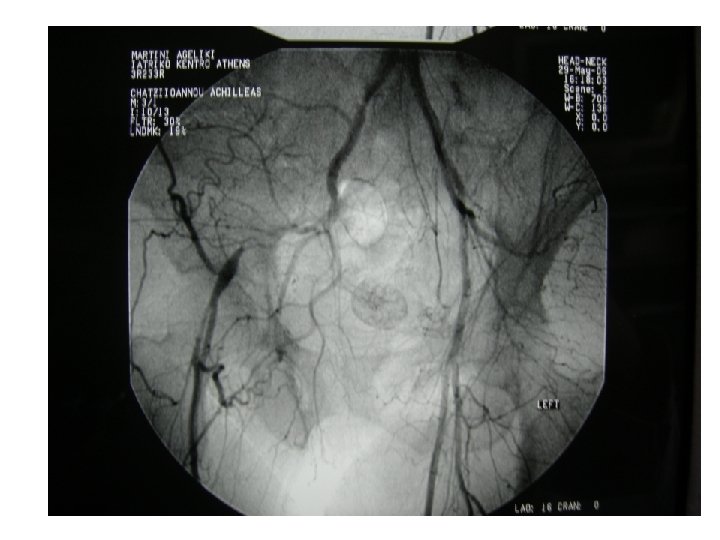

ΕΠΙΛΟΓΗ STENT Carotid angioplasty and stenting

ΕΠΙΛΟΓΗ STENT • • Carotid (self-expandable, braided or nitinol) Vertebral (balloon expandable) Subclavian (balloon expandable) Inominate (balloon expandable) Renal (balloon expandable) Aorta (nitinol, balloon expandable) Common Iliac (balloon expandable, nitinol) Ext. Iliac (nitinol)

Carotid angioplasty and stenting